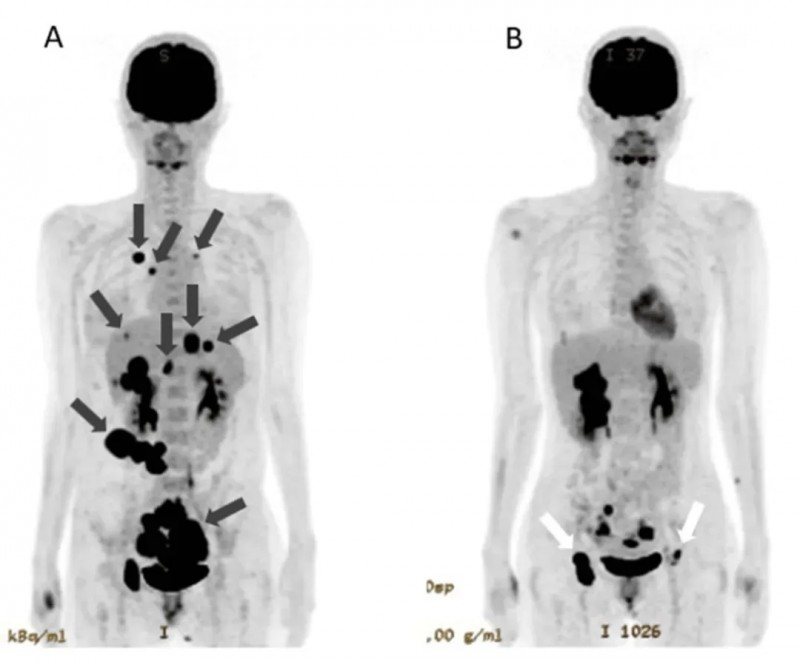

1、全身肿瘤大幅缩小:治疗前PET-CT显示,患者不仅存在原发性卵巢癌病灶,还出现肝脏、肺部、腹膜、骨骼等全身多处转移(详见图1A,黑色箭头标注)。而在接受NK细胞+WT1-DC疫苗+纳武利尤单抗联合治疗的第142天,复查PET-CT结果令人振奋:原发性肿瘤明显缩小,肺转移灶、腹膜播散灶完全消失,肝转移灶显著缩小(详见图1B)。基于肿瘤的明显退缩,患者已具备进行原发肿瘤根治性切除术的条件。

▲图源“Cureus”,版权归原作者所有,如无意中侵犯了知识产权,请联系我们删除